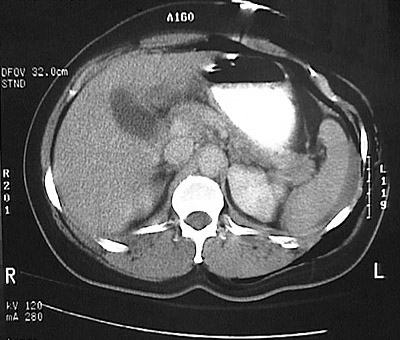

This abdominal CT scan with contrast (filling the stomach) demonstrates a hematoma lateral to a ruptured spleen from blunt force abdominal trauma. The peritoneal lavage yielded bloody fluid, a clue to the diagnosis.